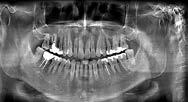

Estudios radiográficos de inicio en la radiografía lateral de cráneo (Figu ra 5) tenemos la clase II esquelética con un ANB de 7°, hiperdivergencia, aumento de la altura facial anterior, disminución de la altura facial poste rior y proclinación del incisivo supe rior con 1 a plano palatino de 121° e incisivo inferior de 1 a plano mandi bular de 99°.

En la radiografía panorámica (Figu ra 6) se observan 32 dientes, con los terceros molares en formación, adicionalmente la molar 46 con una